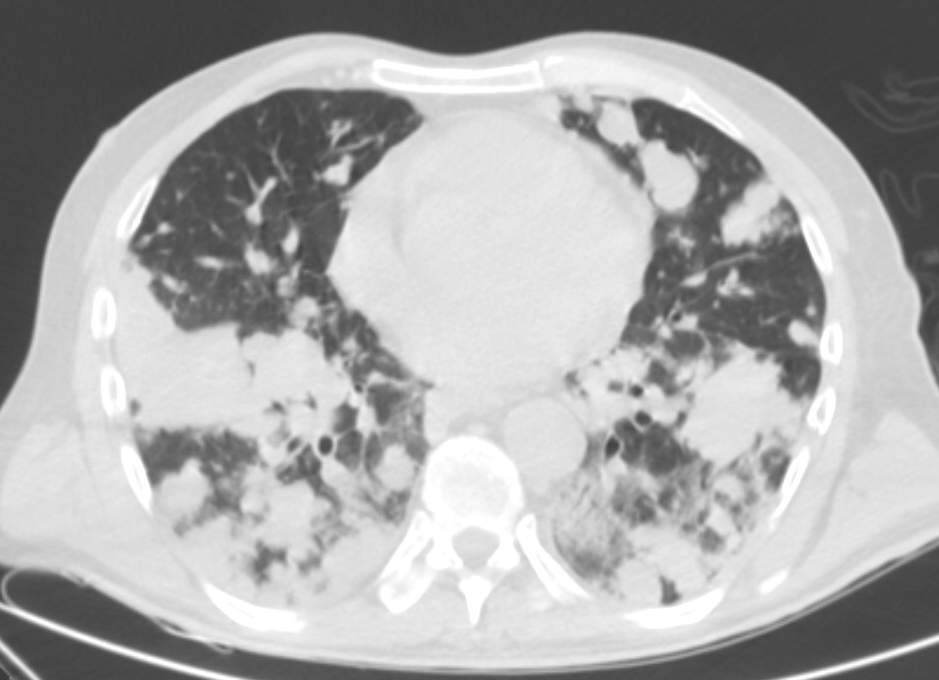

26. ARDS, CT, coronary reconstruction

52 year old woman, dyspnea, septic shock.

Bilateral opacity according to rough, diffuse interstitial edema, irregular atelectasis and bronchogram in the basal segments